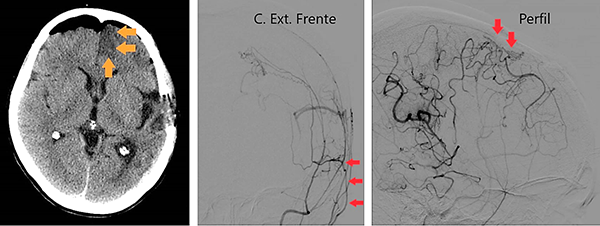

Caso clínico # 2: LD femenino de 51 años con antecedente de tabaquismo e hipertensión arterial, estudiada por deterioro cognitivo de varios meses de evolución. La RMN y ARM evidencia atrofia de hemisferio cerebral izquierdo con hiperintensidad periventricular y disminución franca del calibre de las arterias cerebral anterior y media izquierda con desarrollo de los vasos de MM (Fig. 3). La ADC muestra el stop de la arteria carótida interna izquierda distal y ausencia del origen de las cerebrales anterior y media, buen desarrollo de los vasos de MM y aporte de vasos meníngeos y etmoidales correspondiente a un grado 4 de Suzuki (Fig. 4). Se realizó una revascularización cerebral combinada: un bpTS izquierdo más EDMS y, para aumentar la perfusión en territorio de ambas arterias cerebrales anteriores, un EGPS bifrontal. En la TAC postoperatoria se evidenció un infarto fronto-polar mesial sin repercusión clínica. La ADC postoperatoria diferida evidencia una buena revascularización en los territorios de las arterias cerebral anterior y media a partir del bpTS y la doble sinangiosis (Fig. 5).

Fig. 5 Caso clínico # 2. Postoperatorio. A la izquierda una TAC con pequeño infarto frontomesial. La imagen del centro es una ADC de frente que muestra el bpTS con muy buena perfusión cerebral. La imagen de la derecha es la ADC de perfil que muestra una buena perfusión cerebral a partir de la EGPS bifrontal